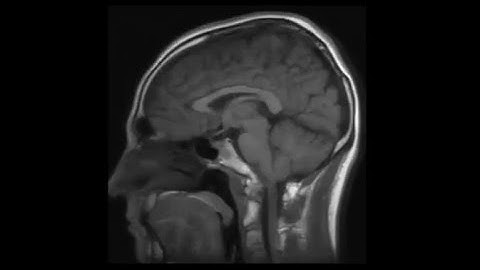

How To 3D Print Your Brain In A Few Simple Steps - TUTORIAL 2022